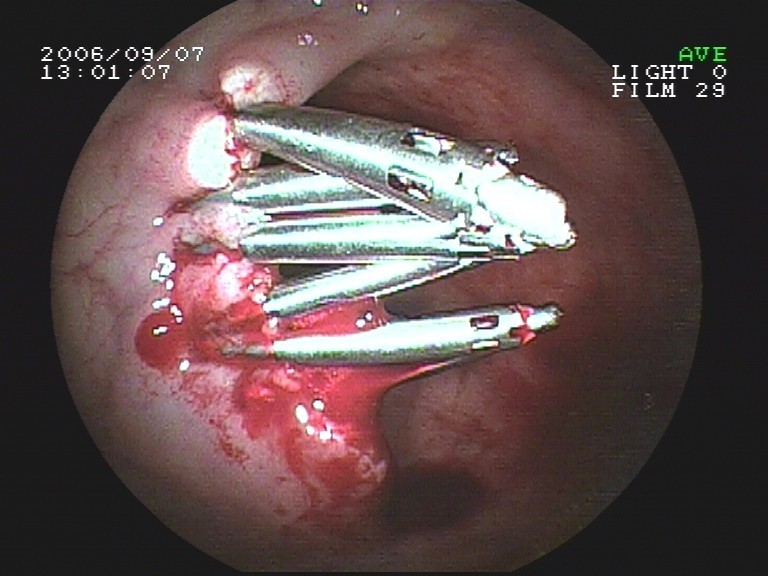

Coloskopie - großer breitbasiger Dickdarmpolyp (Frühkarzinom), Abtragungsstelle nach kompletter Entf